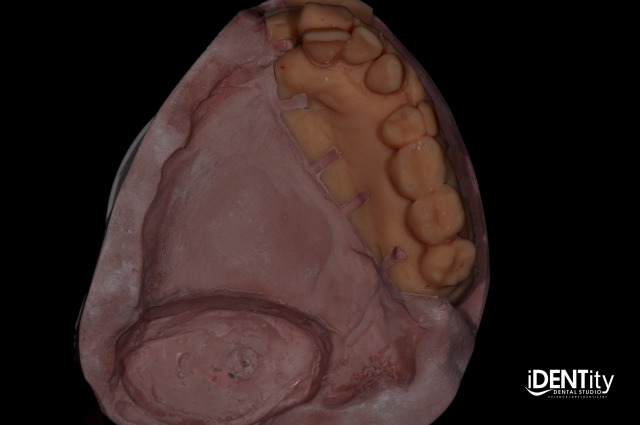

4. Using the printed dental cast of maxillary teeth, the remainder of the palate was removed, and grooves were added to allow conversion to an altered cast.

BrandonStapleton hybrid digitalanalog technique for maxillofacial prosthodontics Fig.3

BrandonStapleton hybrid digitalanalog technique for maxillofacial prosthodontics Fig.4

5. The impression and printed cast were joined and boxed to allow fabrication of a hybrid altered cast.

BrandonStapleton hybrid digitalanalog technique for maxillofacial prosthodontics Fig.5